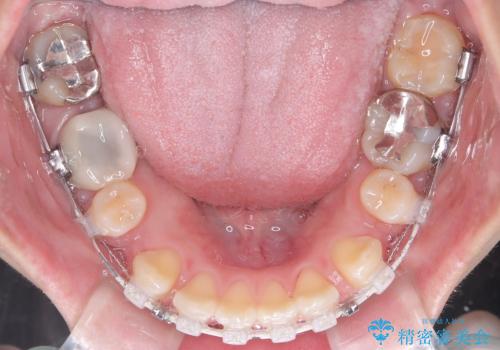

- 口元が出ている(突出している)ことを気にされて来院されました。精密な検査の結果、前歯を大きく後退させるスペースが必要と診断。患者様の**「前歯を下げたい」という強いご要望に応えるため、上下左右の第一小臼歯を抜歯し、そのスペースを利用して前歯を奥へ移動させる治療計画を立案しました。また、人目を気にせず治療できるよう、上顎に裏側矯正、下顎に表側矯正を組み合わせたハーフリンガル矯正**を提案しました。

今回の矯正治療では、前歯を大きく後退させるスペースを確保するため、計画通り上下左右の第一小臼歯を抜歯しました。装置には、上顎には目立たない裏側矯正(舌側矯正)を、下顎には透明な審美ブラケットを使用するハーフリンガル矯正を採用しました。抜歯によってできたスペースを最大限に活用し、前歯を効率よく後方へ移動。治療の結果、口元の突出感が大幅に解消され、Eライン(横顔の美しさの基準)も改善しました。人目を気にすることなく治療を完遂し、自信の持てる美しい横顔を獲得していただけました。